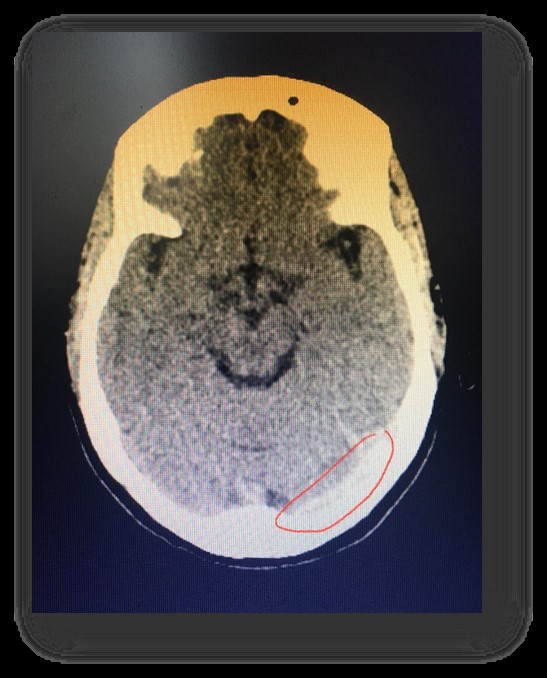

Hình ảnh CLVT và MRI sọ não của bệnh nhân

Trường hợp bệnh nhân nữ 47 tuổi vào Khoa Tâm – thần kinh vì đau đầu sau 02 ngày điều trị tuyến dưới không đỡ. Lúc vào: bệnh nhân tỉnh, đau đầu dữ dội, không có dấu hiệu liệt thần kinh khu trú, không có dấu hiệu màng não, đau đầu tăng dần dùng thuốc giảm đau không đỡ. Bệnh nhân được chụp cắt lớp vi tính sọ não: có hình ảnh dải tăng tỷ trọng nhu mô vùng chẩm bên trái, sau khi thảo luận chúng tôi quyết định chụp cộng hưởng từ não – mạch não thì tĩnh mạch CẤP CỨU, kết quả bệnh nhân bị tắc hoàn toàn xoang tĩnh mạch ngang bên trái. Bệnh nhân đã được đưa về Đơn vị đột quị tiếp tục điều trị ổn định và không để lại biến chứng.